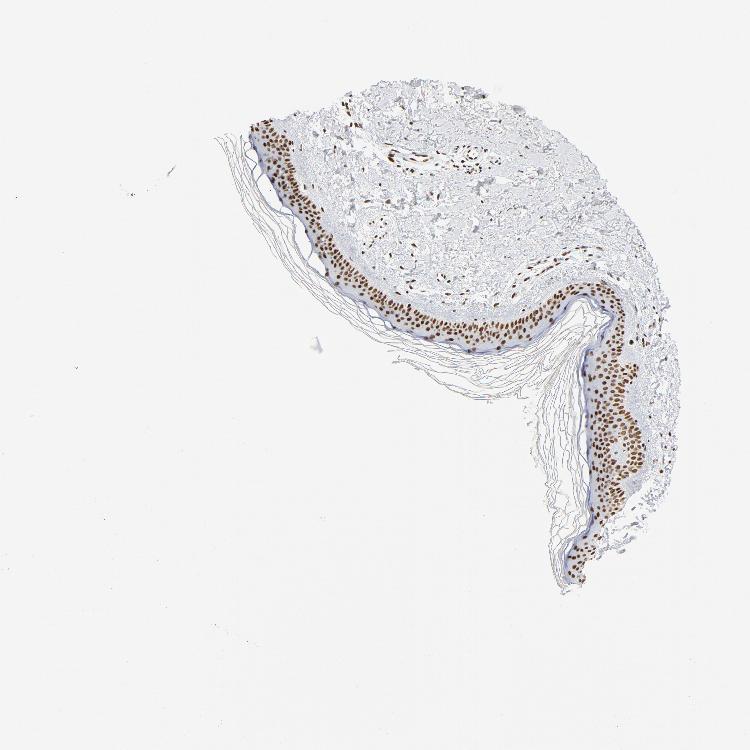

TISSUE PRIMARY DATA SKIN 1 Show tissue menu

SKIN 1 - Antibody stainingi

Antibody staining in the annotated cell types in the current human tissue is reported as not detected, low, medium, or high, based on conventional immunohistochemistry profiling in selected tissues. This score is based on the combination of the staining intensity and fraction of stained cells.

Each image is clickable and will lead to virtual microscopy that enables deeper exploration of all samples and also displays staining intensity scores, fraction scores and subcellular localization as well as patient and tissue information for each sample.

Antibody HPA046660Antibody CAB004637

Langerhans MediumHigh

Fibroblasts -High

Keratinocytes MediumHigh

Melanocytes MediumHigh

SKIN 2 - Antibody stainingi

Epidermal cells MediumHigh